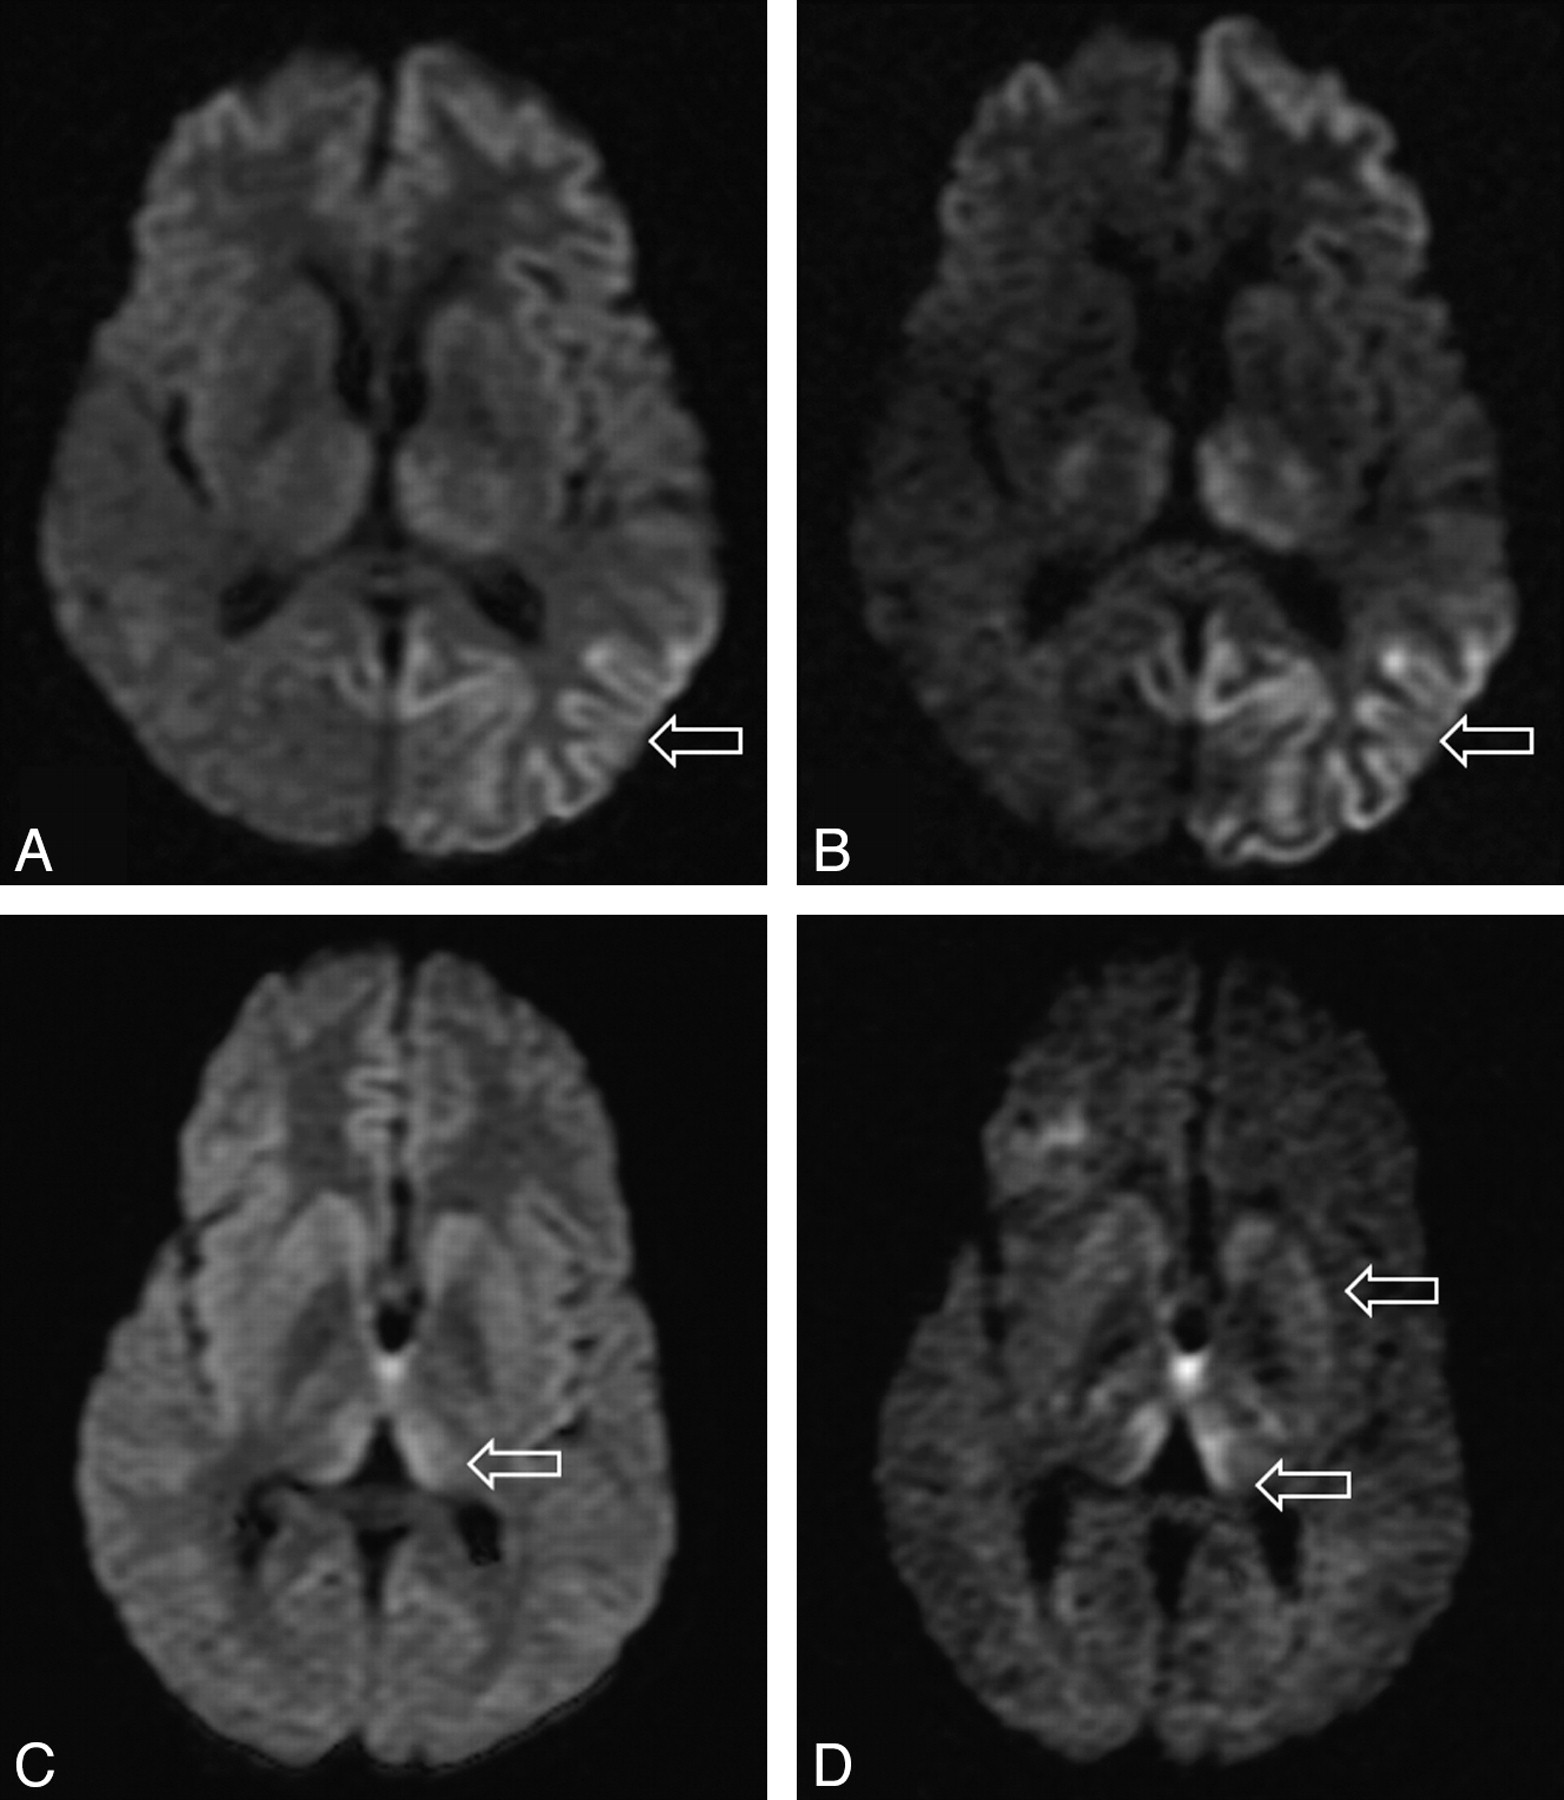

Qualitative Assessment: Comparison of b = 1000 and b = 3000 Images.

In the 10 patients who underwent both b = 1000 and b = 3000 DWI, we found complete agreement between the 2 observers in all cases (κ score 1.0). In 9 out of the 10 cases, SI change was more conspicuous on the higher b-value images. In 1 case the higher b-value image did not aid in assessment, possibly because there were some movement artifacts. In all cases, no new areas of SI change were identified on the higher b-value images, but increased confidence was obtained, particularly for areas that were equivocal on the b = 1000 images (Fig 2). In particular, cortical and thalamic SI changes were more conspicuous at the higher b-value.

Differences in SIs in the basal ganglia in sCJD at (A) b = 1000 and (B) b = 3000 and in vCJD at (C) b = 1000 and (D) b = 3000.

Several recent reports have established DWI as the most sensitive sequence for the diagnosis of sCJD.3–5,20 Visual inspection of the DWI trace-weighted image demonstrates typically increased SI in the cerebral cortex with up to 95% of cases showing hyperintensity affecting the insula, cingulate, and superior frontal cortex independently of deep gray matter involvement.20 DWI is superior to FLAIR in detecting MR imaging cortical SI change, and this has been shown to correlate with lateralized clinical and electroencephalograph abnormalities.21 It is suggested that the anatomic distribution of abnormal hyperintensity affecting the basal ganglia is influenced by PRNP genotype and PrPSc strain type.22,23 However, by using conventional b-values, DWI SI change is not seen in all patients with sCJD.24 We have shown that at high b-values, both cortical and basal ganglia SI changes are better detected on DWI in sCJD, thereby improving confidence in the radiologic diagnosis.

Due to the reported high sensitivity of the Pu sign on conventional MR imaging for the diagnosis of vCJD,25 very few studies have investigated DWI in vCJD. Compared with conventional MR imaging, diffusion-weighted images are less motion sensitive due to their rapid acquisition time, and Pu SI change may be more easily detected on DWI in a restless patient.26 In vCJD, we also found pathologic SI change to be more conspicuous on high-b-value images. Using FWM as reference, we found higher SI ratios at the higher b-values, particularly in the thalamus. This is likely to have contributed to the improved detection of SI change by our observers.